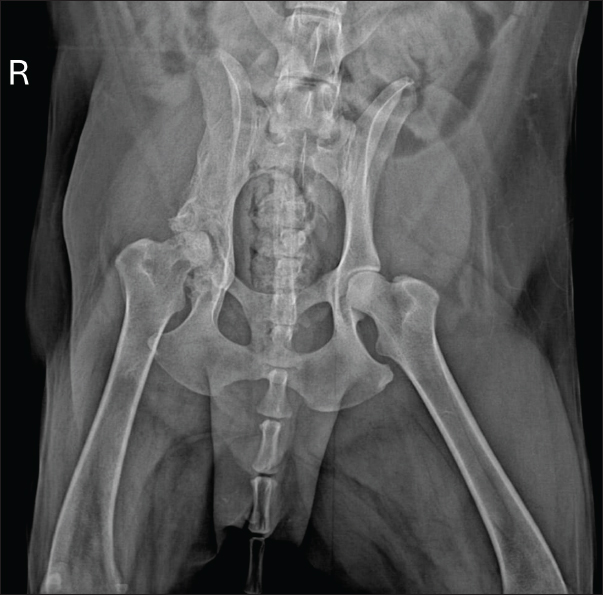

Radiographic examination revealed marked periosteal bone proliferation with extensive areas of osteolysis affecting the wing and body of the ilium, acetabulum, and right femur’s head and neck, along with adjacent soft tissue swelling (Fig. 1).

Fig. 1. Radiographic examination of the dog showing periosteal bone proliferation and areas of osteolysis (arrows) in the right wing and body of the ilium and acetabulum, accompanied by adjacent soft tissue swelling.